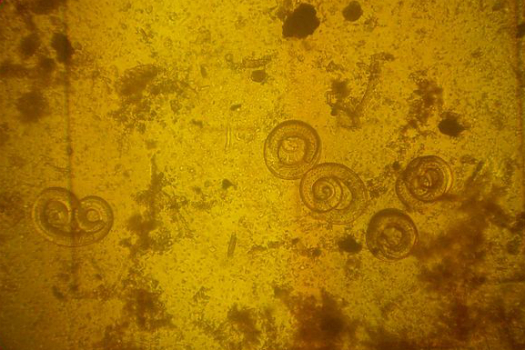

The Case Of The Lost Pork Tapeworm

Common in Africa, Asia and Latin America, adult Taenia solium tapeworms can live inside the human intestinal tract, producing eggs that its human host then expels fecally. As an eye-opening feature in [Discover describes, the eggs can get swept up by pigs as the animals forage for food. The larvae hatch in a pig’s stomach and make their way into its bloodstream, eventually arriving at its muscles, where it will likely be eaten by a human in, say, a pork taco.

But sometimes, the cycle gets interrupted. Someone contaminates food with tapeworm eggs bound for a pig’s stomach. The tapeworm eggs hatch, but instead of developing into an adult tapeworm in the intestines, they burrow into the bloodstream as would normally occur in a pig. In a human, they often end up in the brain, forming cysts that cause a disease called neurocysticercosis. It can cause seizures, headaches and can lead to death. As if you needed another reason to wash your hands.